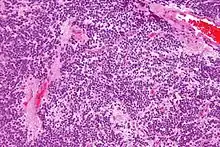

Tumor samples stained using H&E stain and examined under the microscope revealed that CNC is a well-differentiated tumor with benign histological features. The tumor is composed of “uniform, small-to-medium-sized cells with rounded nuclei, finely stippled chromatin and inconspicuous nucleoli, along with scant cytoplasm.” CNC are characterized by perivascular pseudorosettes, circular/flower-like arrangements of cells with a small blood vessel at the centre, and polygonal small cells with a clear perinuclear halo, sometimes called the ‘fried egg’ appearance, and is clear or slightly eosinophilic. The main histomorphologic differential diagnosis is oligodendroglioma. While the tumor cells are dense in some areas, areas with anuclear, less dense tumor parts were dispersed throughout. The anuclear areas may have a fine fibrillary matrix, like that of neuropil regions. Long, thin-walled, capillary-sized vessels represent the vascularity of CNC. These vessels are arranged in a linear branching pattern, with an endocrine appearance. Thin-walled dilated vascular channels, as well as foci of calcification, were readily identified in many cases.[4]

Very high mag.

Very high mag. High mag.

High mag. Very high mag.

Very high mag.